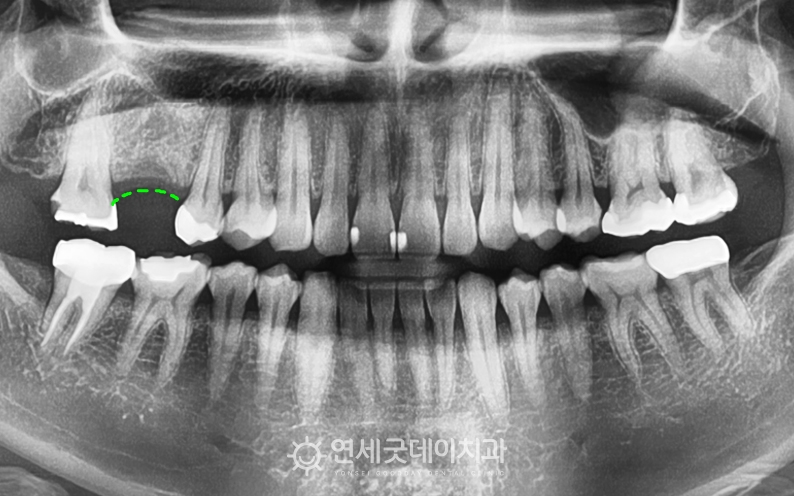

잇몸뼈이식 동반 어금니 임플란트 치료전후 (치과의사 선생님)